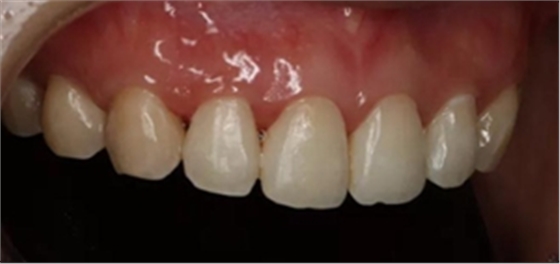

6、去除橡皮章拋光

拋光第一步 用矽粒子去除唇腭側多余樹脂,平整牙面,后使用高級樹脂拋光套裝逐步拋光。這一步目的在于高度拋光樹脂和釉質復合牙面。

術后顯示,滲透樹脂恢復了天然牙釉質的折光率(天然通透牙釉質折光率1.62滲透樹脂折光率是1.52)顯的很自然,很有光澤。完全是天然牙質的顏色。

(下圖是拋光完成)

治療完成的上頜牙齒和未治療的下頜牙齒形成明顯對比。